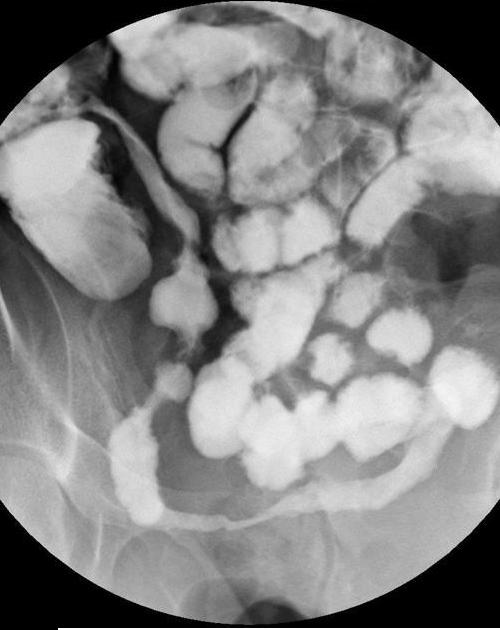

Image radiologique

de lavement baryte du maladie de Cronh est : Au stade precoce : C'est

image de ulceration aphtoide du colon et lesions nodulaires

en associees . Au stade tardif image de stenose serre du

colon et ileon ou de l'intestin grele en segmentaire ,avec image de fistule ou image

de sacculaire peut se voyait et l'intestin en amont est

dilate .Aspect echographie percutanee

Maladie de Crohn ileo-colique

: Lesions nodulaires sur le colon transverse et

ceaco-ascendant Image radiologique de

lavement baryte en double de contrast |

Aspect d'ulceration aphtoides sur

le colon transverse et sigmoide ( fleche noire ) ;

|

Image stenose et lesion

ulcere en fissure de ileon peut voyait si net

sur le lavement baryte en double de contrast du

colon . |